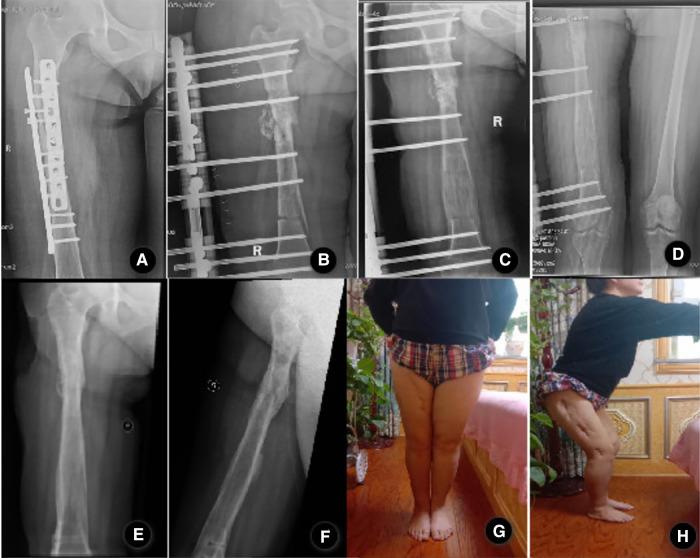

The rail fixator can improve the treatment outcome and provide good stability in patients with femoral bone transport. The purpose of this study is to investigate the clinical outcomes of bone transport using the Ilizarov technique by rail fixator in the treatment of femoral nonunion or bone defects caused by infection.

Clinical feature and treatment outcomes of 32 consecutive adult patients with femoral nonunion or bone defect caused by infection from January 2012 to January 2019 at a minimum of 2 years of follow-ups were retrospectively analyzed. Data were collected on participants' demographic details. All difficulties related to bone transport were documented according to Paley's classification. The clinical outcomes were evaluated using ASAMI criteria at the last clinical visit.

All 32 patients with an average follow-up of 33.5 months. There were 17 problems, 21 obstacles, and 8 complications, and the complication rate per patient was 1.4. The main complications were pin-site infection (53.1%), axial deviation (21.9%), joint stiffness (18.8%), the delayed union of the docking site (18.8%), soft tissue incarceration(15.6%), delayed consolidation(6.3%), malunion(6.3%), and refracture (3.1%). All the patients achieved bone union, and no recurrence of infection was observed. The excellent and good rates of ASAMI bone and functional results were 87.5% and 81.3%, respectively.

Bone transport using the Ilizarov technique is an effective method for the treatment of femoral nonunion or bone defect caused by infection, and rail fixators have obtained satisfactory results in terms of bone and functional results.